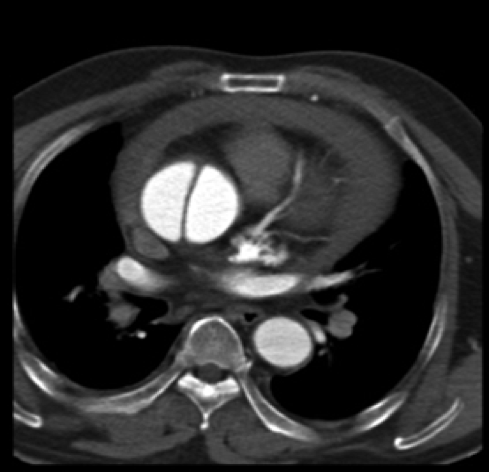

4、主动脉夹层怎么诊断?

突发剧烈胸背痛,特别是伴有血压明显增高者,都需高度警惕主动脉夹层可能。主动脉增强CT是确诊主动脉夹层撕裂的极好方法,且可以迅速完成。

图片 3.png

主动脉CTA

图片 4.png

主动脉CTA明确诊断